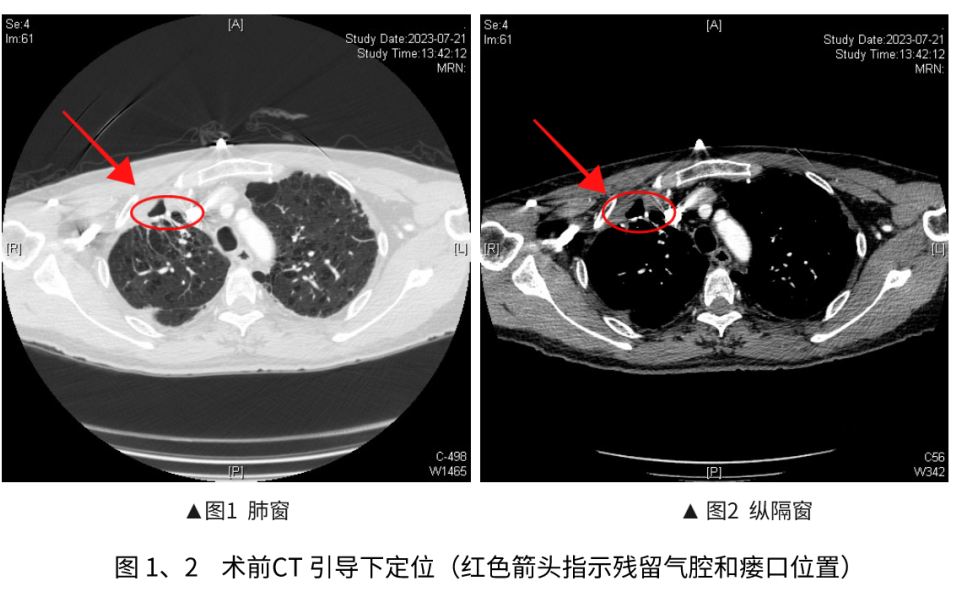

内科胸腔镜下微创技术包括:肺大疱减容、难治疗性气胸、支气管胸膜瘘修补。